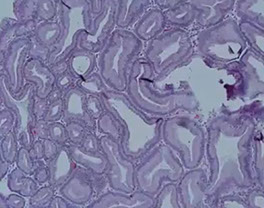

AJCC staging Gastric cancer